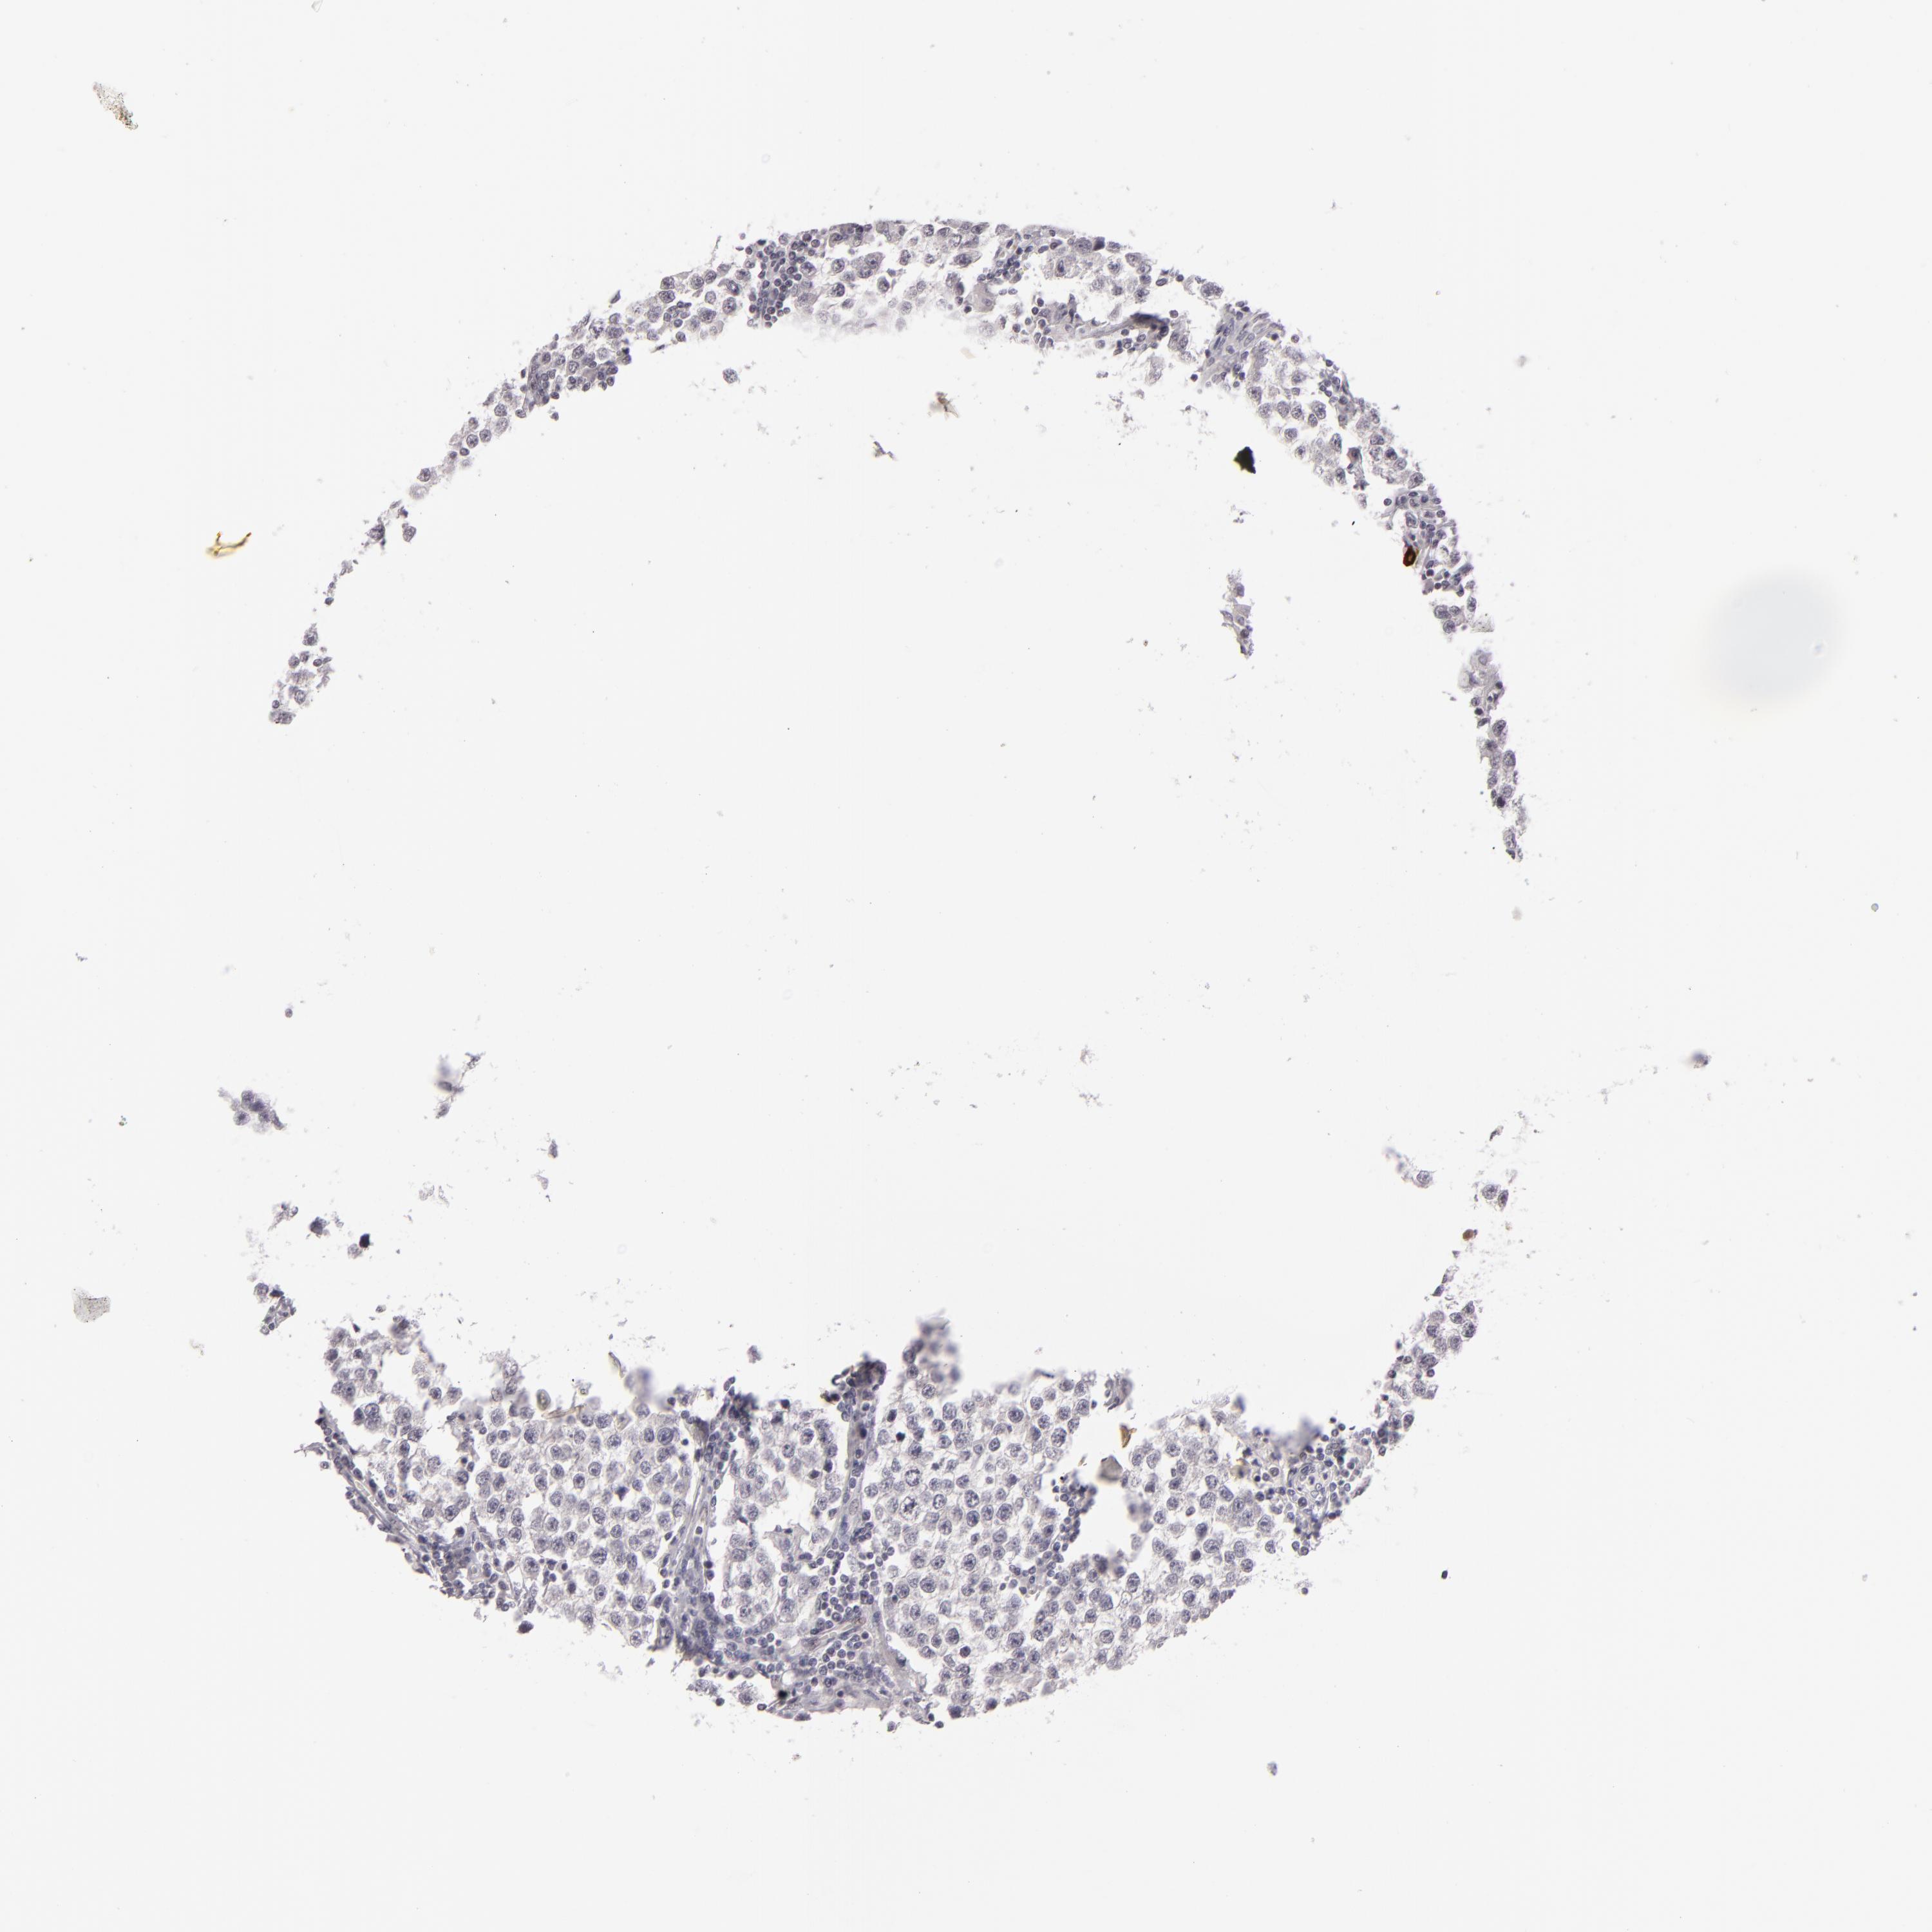

TESTIS CANCER - Protein expressioni

A mouse-over function shows sample information and annotation data. Click on an image to view it in a full screen mode. Samples can be filtered based on level of antibody staining by selecting one or several of the following categories: high, medium, low and not detected. The assay and annotation is described here.

Note that samples used for immunohistochemistry by the Human Protein Atlas do not correspond to samples in the TCGA dataset.

Antibody stainingi

Antibody staining in the annotated cell types in the current human tissue is reported as not detected, low, medium, or high, based on conventional immunohistochemistry profiling in selected tissues. This score is based on the combination of the staining intensity and fraction of stained cells.

Each image is clickable and will lead to virtual microscopy that enables deeper exploration of all samples and also displays staining intensity scores, fraction scores and subcellular localization as well as patient and tissue information for each sample.

Antibody HPA001791

Staining

High

Medium

Low

Not detected

Intensity

Strong

Moderate

Weak

Negative

Quantity

>75%

75%-25%

<25%

None

Location

Nuclear

Cytoplasmic/membranous

Cytoplasmic/membranous,nuclear

Seminoma, NOS

Carcinoma, Embryonal, NOS